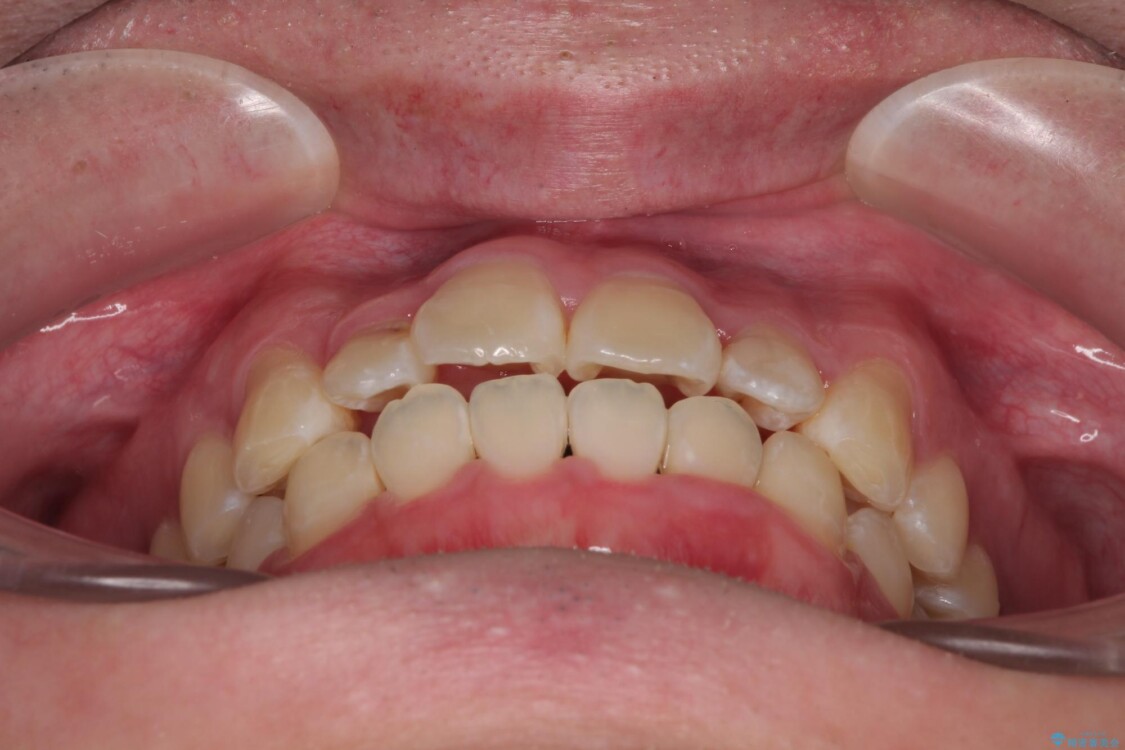

治療後について

適切な診断と装置の選択により、1年という短期間でここまで改善できます。

見た目の美しさだけでなく、将来のむし歯や歯周病リスクを減らすことにもつながる治療です。

治療後

• 1年でここまで変わる!歯列のがたつきと正中のズレを改善した矯正治療(メタルブラケット×MARPE) 治療後画像